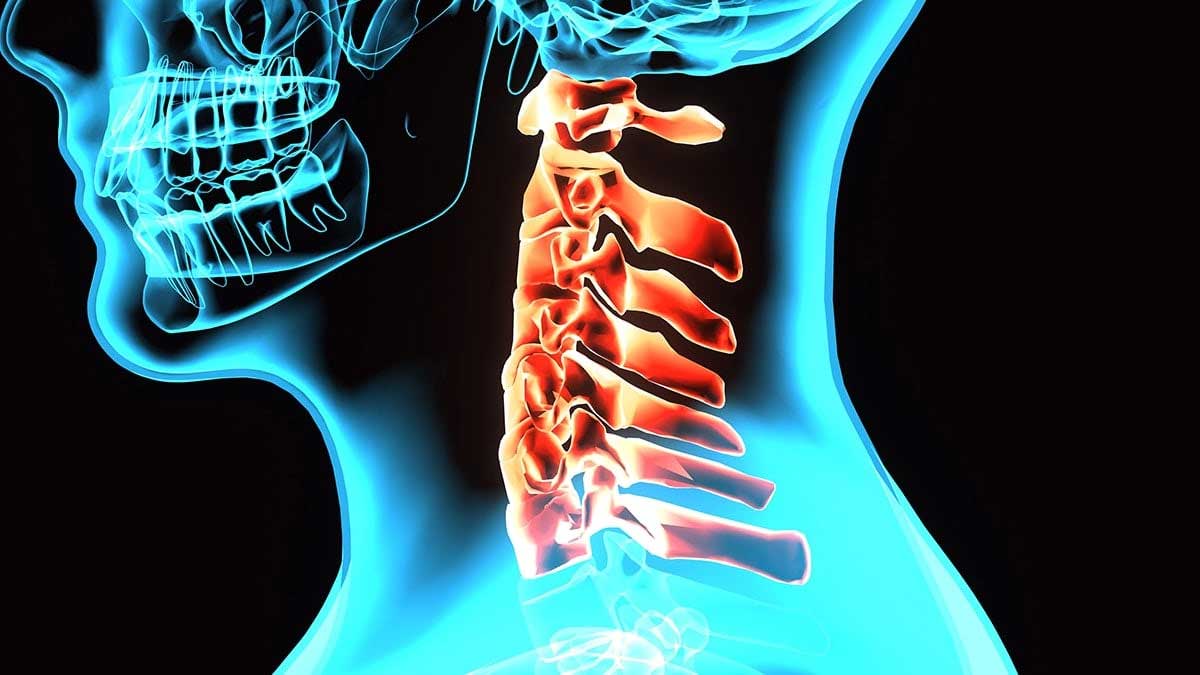

A broken neck, medically referred to as a cervical spine fracture, is one of the most serious traumatic injuries a person can experience. The cervical spine consists of seven vertebrae (C1–C7) that support the head, protect the spinal cord, and allow for a wide range of motion. When any of these vertebrae fracture or become unstable, the consequences can be life-altering. Doctors emphasize that the true danger often lies not only in the fracture itself but in the Complications of a broken neck, which may affect nearly every system in the body.

A broken neck typically results from high-impact trauma such as car accidents, falls from height, sports injuries, or violent incidents. In older adults, even minor falls can cause fractures due to osteoporosis. The cervical spine houses and protects the upper portion of the spinal cord, which transmits signals between the brain and the rest of the body. Damage in this region can disrupt breathing, movement, sensation, and organ function.

The severity of injury varies widely. Some fractures are stable and may heal with immobilization using a cervical collar or brace. Others are unstable and require surgical intervention to prevent spinal cord damage. Doctors categorize injuries based on their location, mechanism, and associated neurological involvement. When the spinal cord is compressed or severed, the risk of severe Spinal cord injury complications increases dramatically.

One of the most feared Complications of a broken neck is spinal cord damage. The cervical spinal cord controls movement and sensation in the arms, trunk, and legs, as well as diaphragm function. Injury at higher cervical levels (C1–C4) may impair breathing, requiring mechanical ventilation.